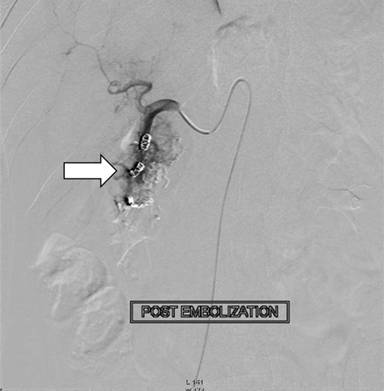

The patient had recurrence of upper gastrointestinal bleeding three days after the endoscopic intervention, requiring transfusion of two more units of packed red blood cells. He was taken up for emergency endoscopy which revealed bleeding ulcer in the proximal duodenum and a repeat session of injection sclerotherapy was done; however, the bleeding did not stop. In view of continuing bleeding, the patient underwent conventional angiography which revealed a diffuse vascular blush in the head of the pancreas (Figures 4 and 5) with early filling of the veins suggestive of tumor blush. Feeder from the gastroduodenal artery was embolized with gelfoam and coil. Check angiography showed no early filling of veins. Superior mesentery artery angiogram showed similar blush in the same region but could not be embolized.

|

Figure 5. Selective celiac axis angiography post embolization. |